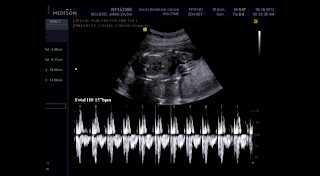

Hey everyone!! Today is the ultrasound day!  I woke up at 5:30 this morning and I was too nervous and excited to go back to sleep. Apparently, Hubs had troubles sleeping at all and he told me that he only slept a few minutes here and there. We rolled out of bed after being too lazy to get up around 6 something. Hubs got Princess up while I got dressed. I tried to eat breakfast and I had a little bit of tea. we walked out the door late (like normal).  After picking up my mom we were on our way to see the Little Bean. We meet Hubs's parents there. Waited maybe  10 minutes if that to go back in to get the ultrasound.  So excited!! Hubs said that it would be s lot of fun to announce to everyone on here the gender and I think it would be too. Yes actually I am stalling lol. For those of you who are coming in from our Facebook profiles there is a rule. You are not to comment on our Facebooks yet about what the gender is and if you do it will get deleted. However, you can call us, text us, or even comment on here. Sorry but we want to keep this fair for everyone and I don't want people to cheat lol.

The moment we have been waiting for!!

It's a Girl!!

Her name is going to be Elizabeth Fayelynn Arwyn!